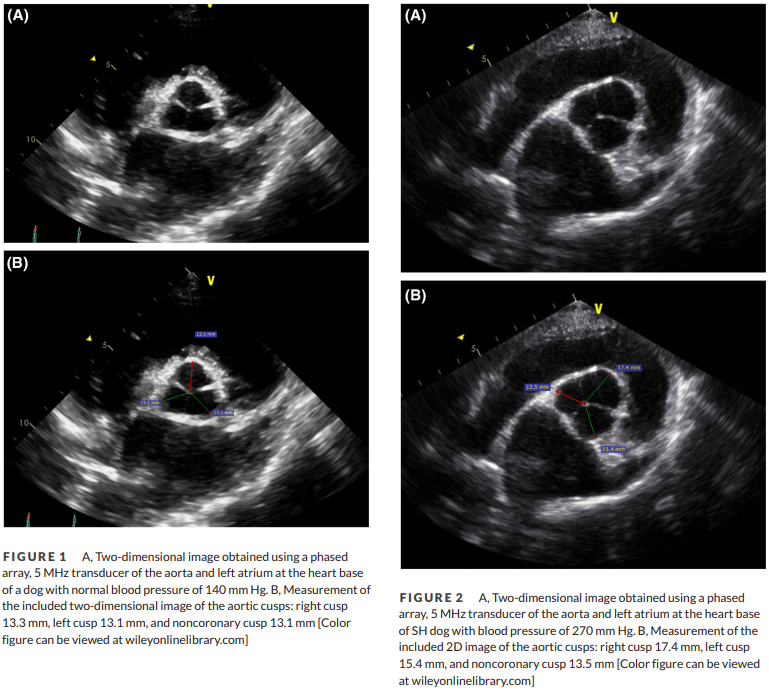

심장초음파 검사시 전신고혈압의 의심 point

판막 대칭성이 감별의 point 라는 말

하지만 정성평가일 뿐이고 혈압은 심장 초음파 검사전 이미 측정되어 있어야 하니

그냥 그러하다는 의미의 논문